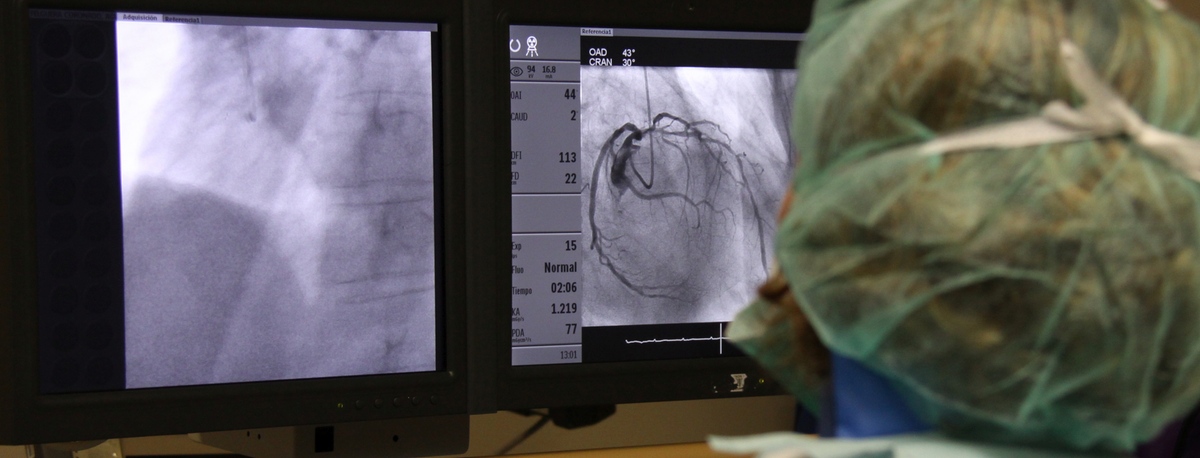

Teknon Cardiology Institute

Experience treating cardiovascular diseases